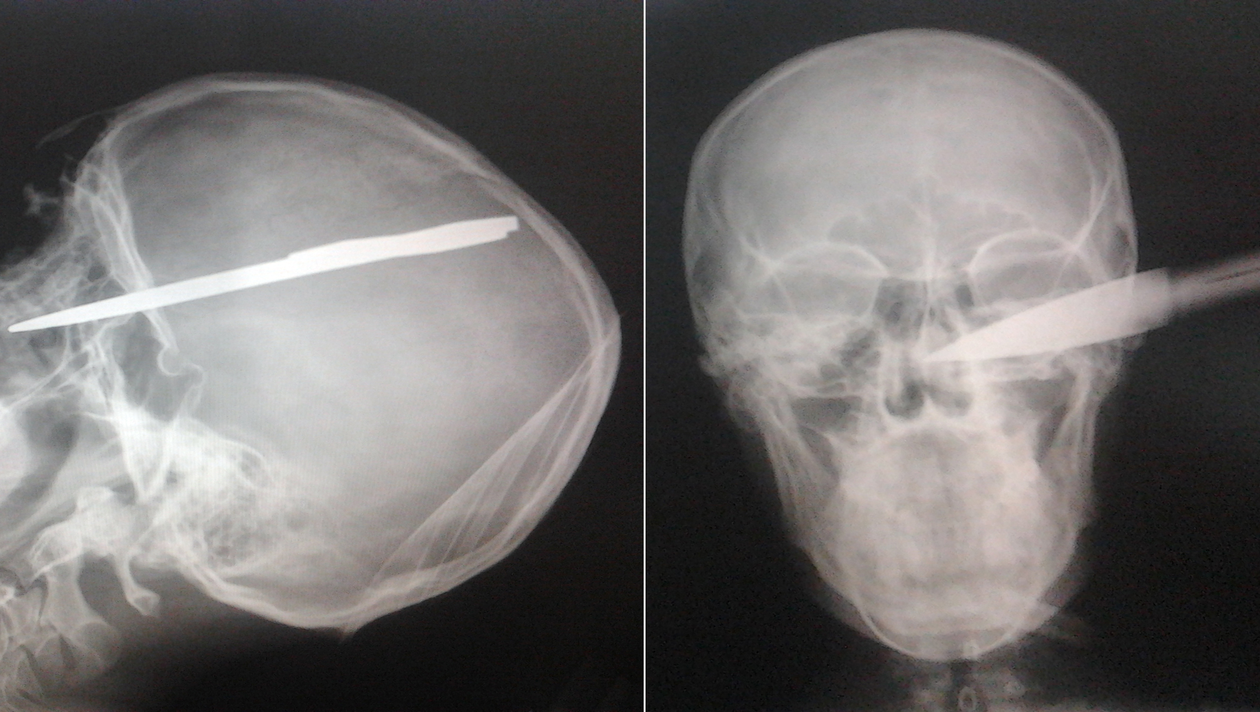

Un tanar de 20 de ani a uimit medicii! Barbatul a ajuns la spital cu o sabie efectiv infipta in cap! Dupa o operatie care a durat 45 de minute, verdictul a fost incredibil: leziunile au fost minore, iar in patru zile omul a plecat acasa!

I.A.G. (20 de ani) a fost externat din spital dupa patru zile si va ramane, cel mai probabil, in istorie drept barbatul care a trait dupa ce o sabie i-a fost infipta in cap. In ciuda faptului ca lama armei i-a patruns in craniu aproximativ sase centimetri, nici un element vascular nu a fost atins, au sustinut surse medicale.

Scandalul s-a petrecut noaptea, iar unul dintre inculpati a lovit victima cu intentia de a o omori. Cert este ca planurile le-au fost date peste cap de …destin! Barbatul care parea sa nu aiba nicio sansa de supravietuire, a scapat aproape nevatamat si dupa patru zile a fost externat. Radiografia e socanta si arata cat de aproape a fost, de fapt, tanarul de moarte si ce miracol e ca a supravietuit. (A.S.)